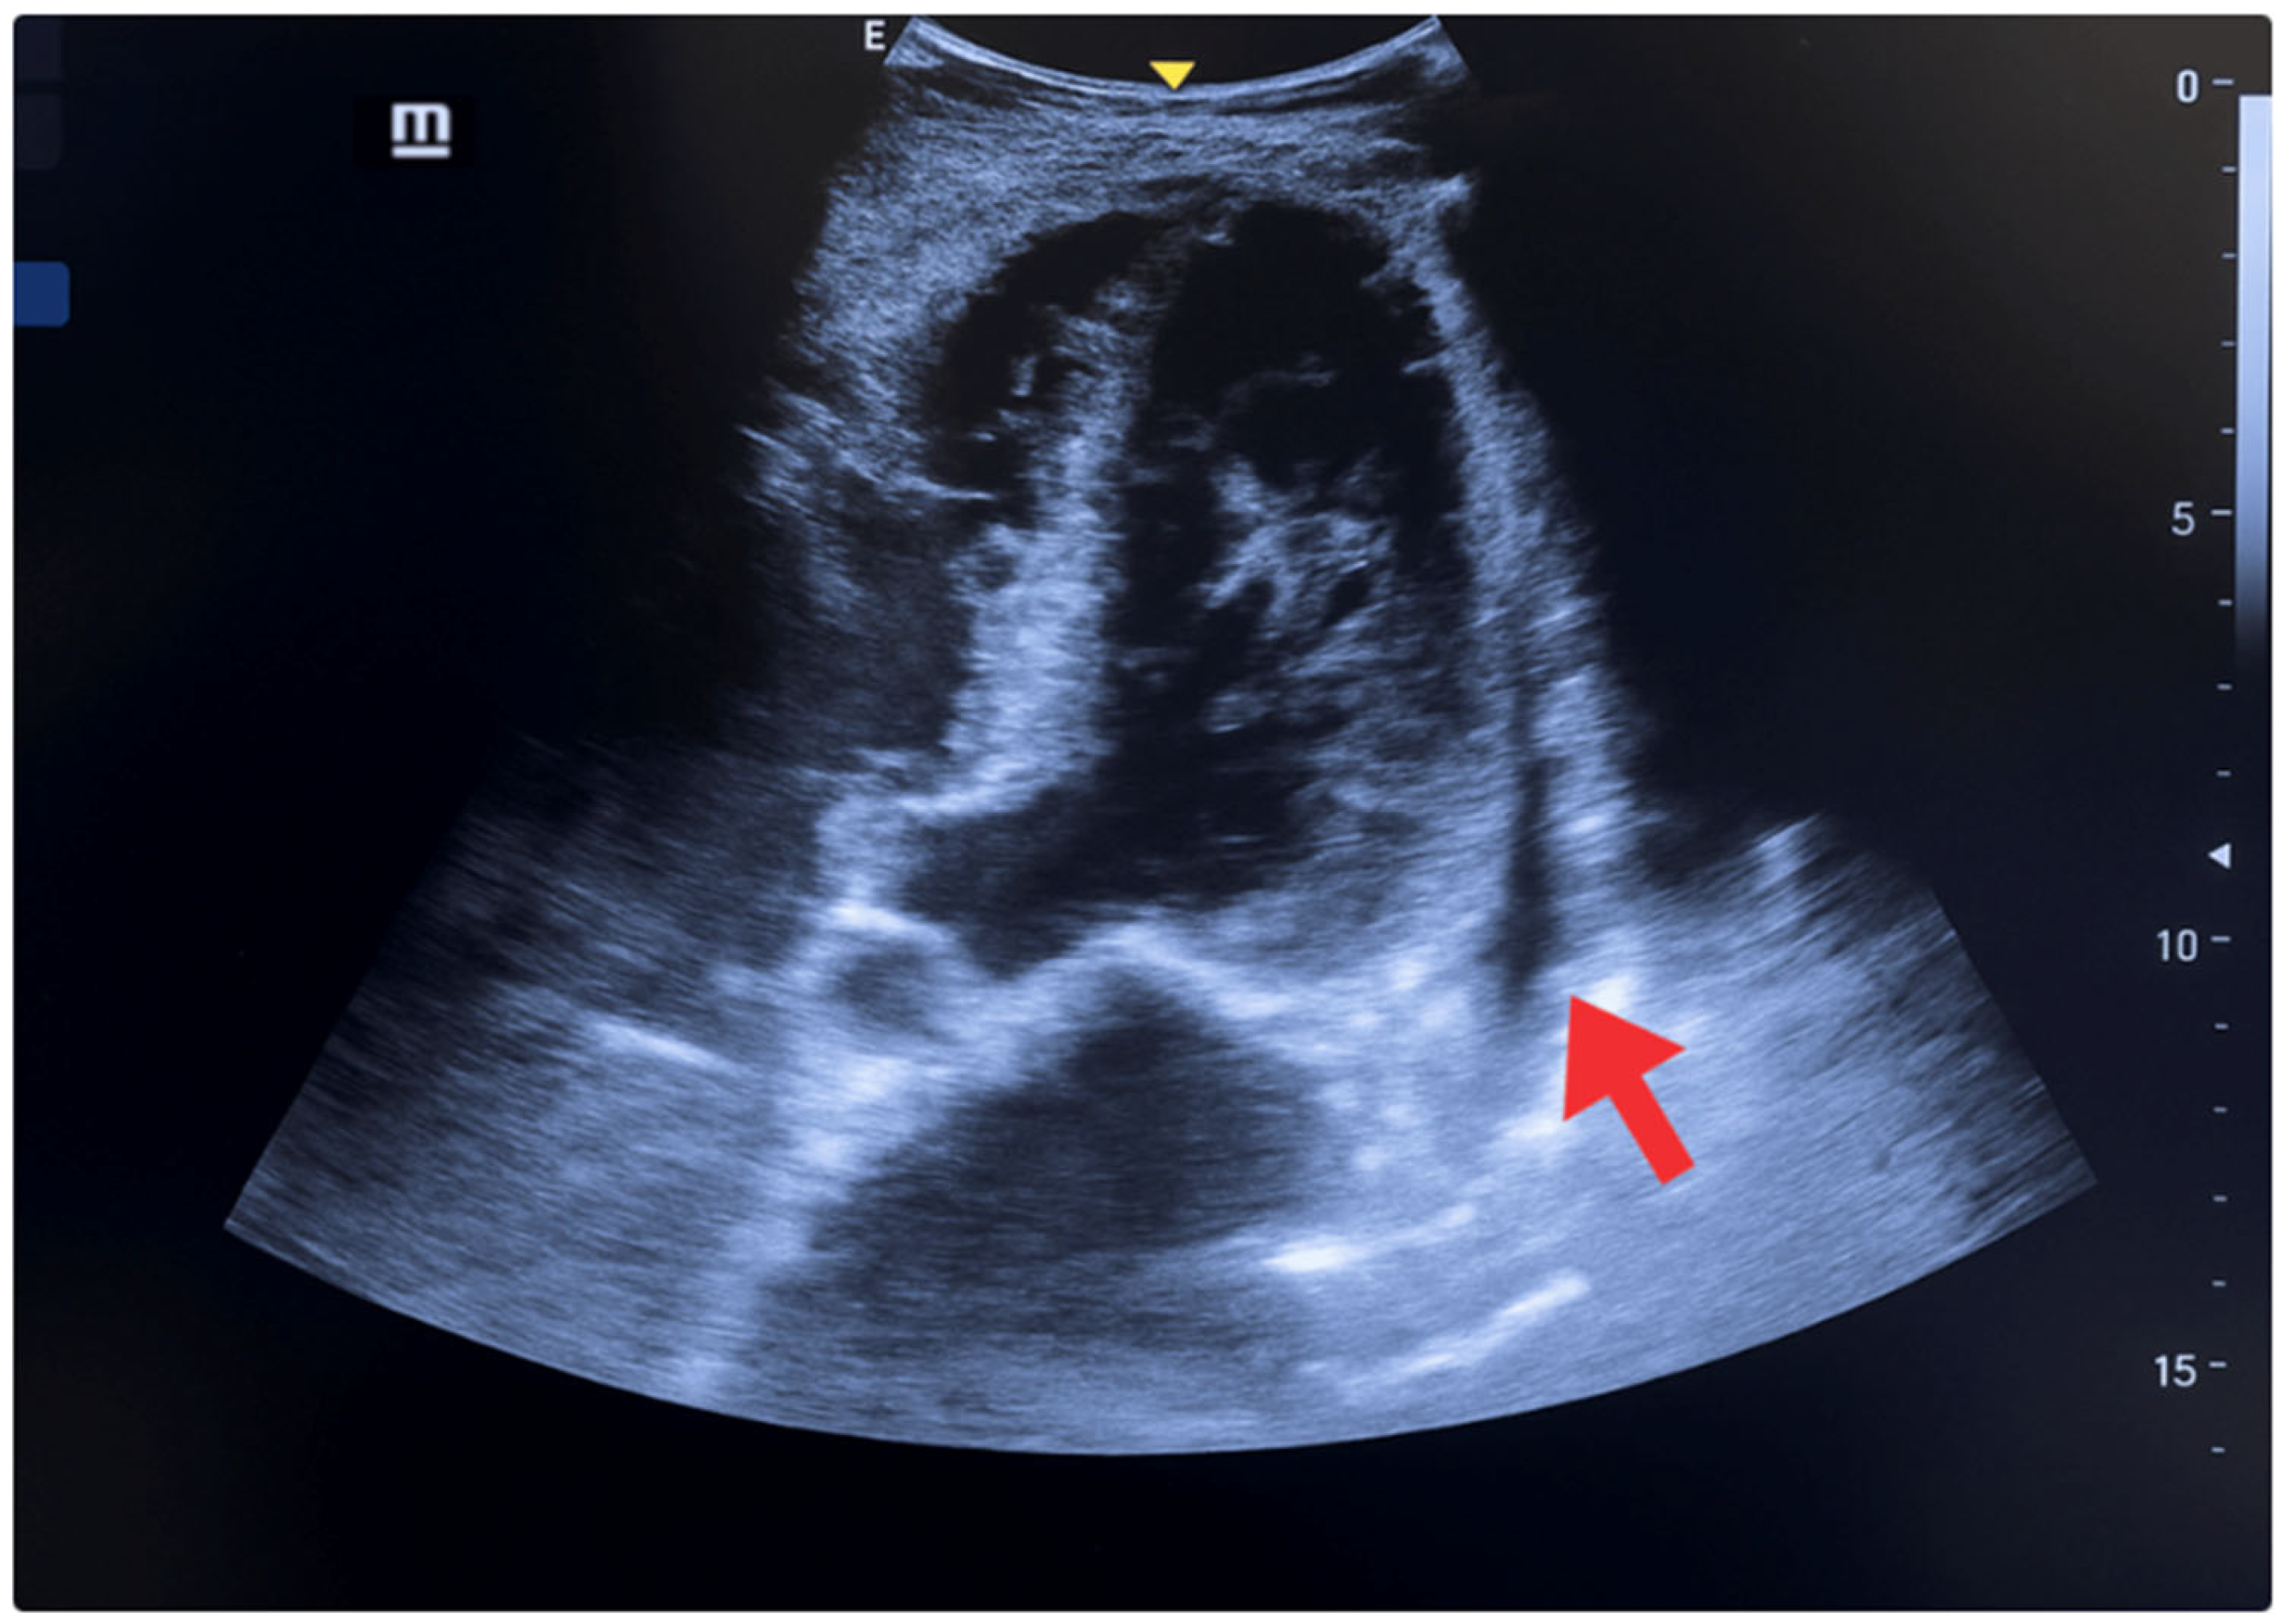

| 5 May | Acute episode of oppressive retrosternal chest pain (30 min, 8/10), with sudden moderate dyspnea, nausea, and profuse diaphoresis. He presented to the primary emergency department. Initial evaluation: BP 160/85 mmHg, SatO2 85%, signs of pulmonary and peripheral congestion. | -ECG: Biphasic T waves were present in the anteroseptal leads (V2–V4), consistent with a type A Wellens pattern. -Laboratory: elevated troponin I (0.16 ng/mL), (reference < 0.03 ng/mL). | POCUS: Ejection fraction of 40% (moderate systolic dysfunction), shortening fraction of 18%, EPSS of 10 mm, lateral wall hypokinesia, eccentric remodeling with ventricular dilatation, thickened interventricular septum, and a small non-circumferential pericardial effusion. At the lung level, diffuse B lines (50–60% of lung fields) were present, a pattern consistent with alveolar-interstitial syndrome of cardiogenic origin. | Initial treatment: oxygen, IV nitroglycerin, ASA 300 mg PO, clopidogrel 300 mg PO, rosuvastatin 40 mg PO, IV furosemide. |

| 6–7 May | Mild retrosternal chest pain, absence of dyspnea, and improved ventilatory mechanics. | ECG: Biphasic T waves were present in the anteroseptal leads (V2–V4), consistent with a type A Wellens pattern. | POCUS: Decreased pulmonary B lines in both lung fields (40–50%). | Referral to a more complex center. Enoxaparin 80 mg SC every 12 h is added. |

| 9–11 May | Hospital stay in an intermediate care unit. | ECG: -Rhythm: sinus (positive P wave in L1, L2, and aVF; each P wave is followed by a QRS complex). -Heart rate: 80 beats per minute. -Electrical axis: between (−60° left axis deviation). -P wave: duration ≤ 120 ms, amplitude ≤ 2.5 mm in limb leads. PR interval: 160 ms. -QRS complex: duration ≤ 110 ms. -ST segment: isoelectric. -T wave: positive in most leads, except aVR and V1. -Corrected QT interval (QTc): 400 ms. -Findings of left ventricular hypertrophy. | POCUS: -Absence of pulmonary and cardiac congestion. -Regular pleura, without thickening. -Marked reduction in B lines (<20%) in affected lung fields. -Reappearance of predominant A lines. -Absence of consolidation. Findings compatible with resolution of cardiogenic alveolar-interstitial syndrome after depleting therapy. -Ejection fraction (Simpson): 50–55% -EPSS: 7 mm (previously 10 mm). -Shortening fraction: 25%. -Less evident lateral hypokinesia. -Left chambers with reduced diameter and indexed end-diastolic volume (≤70 mL/m2). -Mild, stable, non-progressive pericardial effusion. | - |